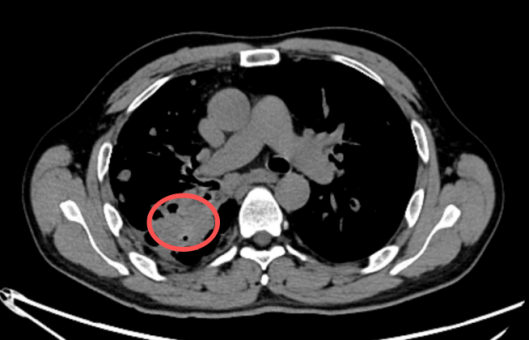

图示:右上肺病灶内局部可见两枚结节状血管样强化灶,与肺动脉相连,较大者直径约 6 mm